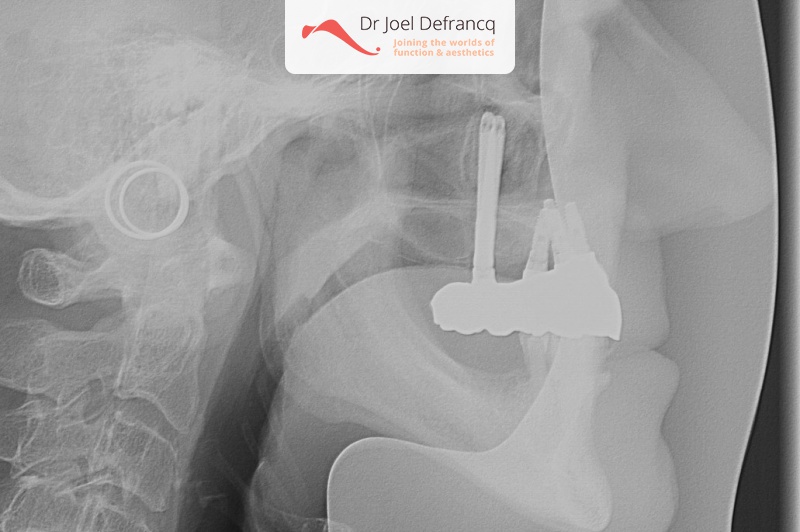

Behandeling tandheelkundige implantaten

- Vaste tanden op implantaten (bovenkaak)

- Zygoma implantaten